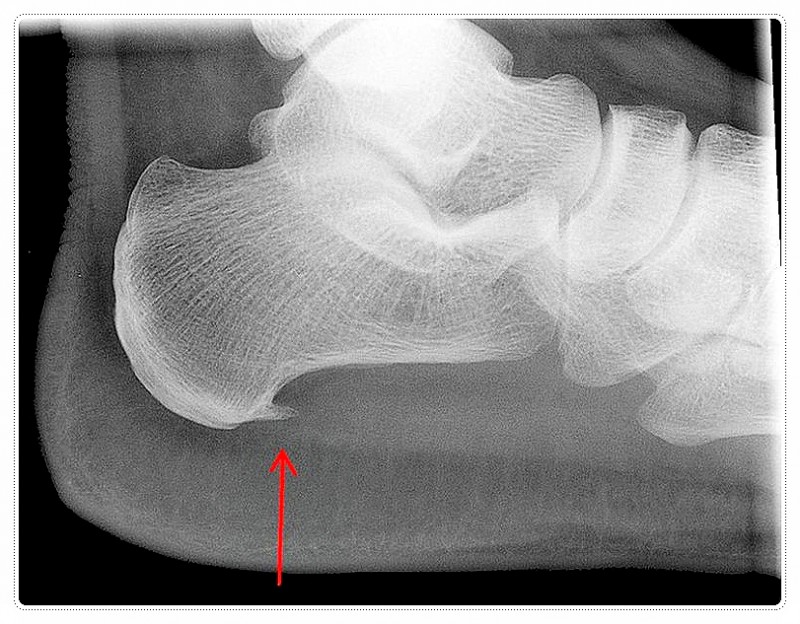

요족은 발의 아치가 정상보다 높아 체중이 발 전체에 고르게 분산되지 않는 상태를 말합니다.

이 경우 발바닥이 바닥을 지지하는 면적이 줄어들면서, 압력이 발뒤꿈치나 앞쪽 발바닥에 집중되는 경우가 많습니다.

그 결과 보행 시 충격을 제대로 흡수하지 못하고, 특정 부위부터 통증이 시작되기 쉬워지지요.

아치가 높은 발에서는 족저근막에 반복적인 긴장이 가해지기 쉽습니다.

이로 인해 아침에 첫 발을 디딜 때 통증이 심하거나, 운동 후 통증이 두드러지는 족저근막염으로 이어지는 경우도 적지 않습니다.